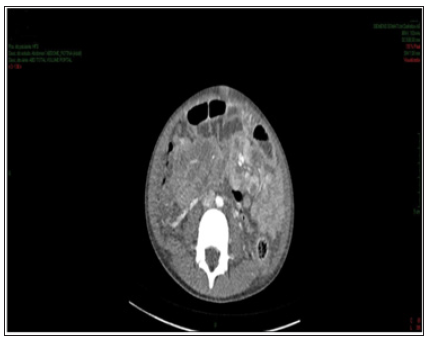

Figure 3: Contrast-enhanced abdomen CT showing hypodense, hypocaptant mass of ill-defined limits on the right flank, compatible with lymph node mass.

Enhanced abdominal CT performed on the 1st day of hospitalization, revealed enlarged liver, with heterogeneous attenuation, at the expense of diffuse, ill-defined, sparse hypodense images, measuring up to 2.4 cm in segment II. Mild dilation of the intrahepatic bile ducts. Spleen enlarged, heterogeneous texture, at the expense of diffuse hypodense images. A hypodense, amorphous, poorly delimited (Figure 1). Expansive formation located in retroperitoneum and mesenteric root with involvement of the mesenteric vessels, without determining stenosis of the same, consistent with lymph node conglomerate. Prominent para-aortic lymph nodes, measuring up to 2.6 x 1.4 cm (Figure 2). Moderate amount of free fluid in the abdominal cavity. Hypodense and hypocaptant mass of ill-defined limits on the right flank, compatible with lymph node mass (Figure 3). In chest CT no lymph node enlargement was been in the mediastinum. On the 3rd day of hospitalization, abdominal ultrasonography was also performed to corroborate the CT findings, evidencing an enlarged liver, diffusely heterogeneous with small hypoechoic solid nodules distributed in the hepatic parenchyma. Heterogeneous pancreas, with presence of solid hypoechoic nodule, adjacent to the body, measuring 2.3 cm, suggesting lifonodomegaly. Enlarged spleen with presence of multiple hypoechoic solid nodules of small dimensions. Moderate ascites. Solid mass on the right flank measuring approximately 10 cm suggestive of confluent lymph nodes. The left inguinal lymph node biopsy was analyzed by the simple “imprint” and “cell block”, the macroscopy of which describes a brownish, lobed and unctuous fragment measuring 1.3 x 0.6 x 0.4 cm. Microscopy showed a chronic/acute granulomatous inflammatory process containing multinucleated giant cells in the lymph node tissue. Special coloring by the PAS and Grocott method evidenced fungal structures suspected of Paracoccidioides (Figures 4 & 5).